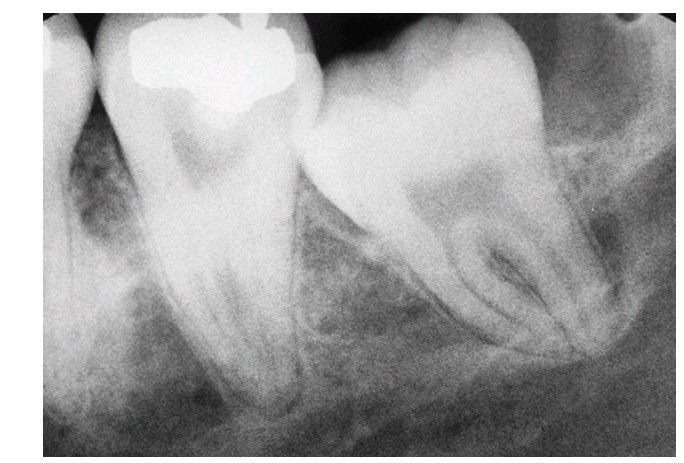

Wide periodontal ligament space

. The widened space makes the extraction process less difficult.